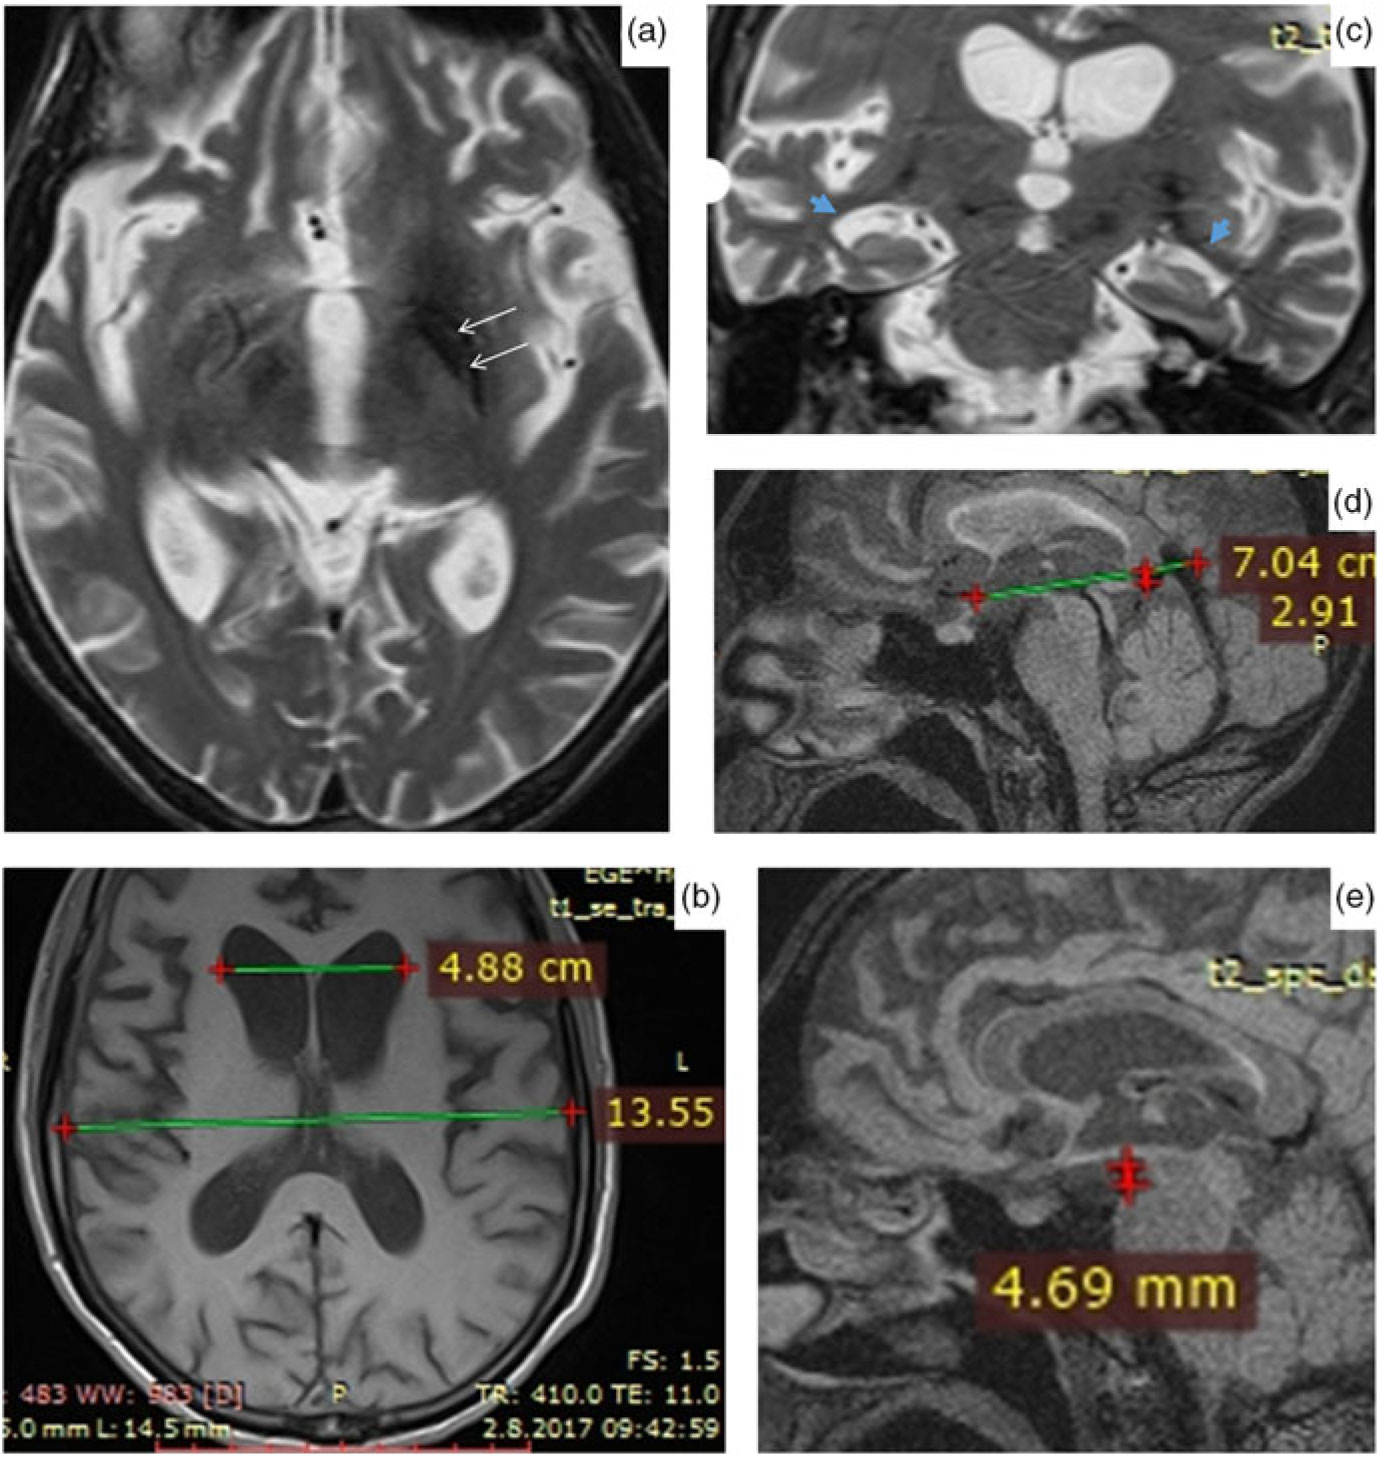

The brain magnetic resonance imaging (MRI) revealed bilateral hypointensities in globus pallidus and substantia nigra, mild brain atrophy and enlargement in temporal horns of lateral ventricles (Figure 2). Medullary lamina was prominent specifically on the left side on T2-weighted MRI. Evans index was 0.35, suggesting hydrocephalus. Mamillopontine distance was decreased, measured as 4.7 millimeters (mm). Spleniochiasmal distance was decreased, measured as −2.9 mm.

Figure 2: Magnetic resonance imaging findings. (a) Prominent medullary lamina specifically on the left side. (b) Calculation of Evan's index. (c) Enlargement in lateral ventricle temporal horns (blue arrows). (d) Calculation of mamillopontin distance. (e) Calculation of spleniochiasmal distance.

Hartig et al.Reference Hartig, Iuso and Haack 1 and Olgiati et al.Reference Olgiati, Doğu and Tufekcioglu 3 observed bilateral hypointensities in globus pallidus and substantia nigra on T2- or susceptibility-weighted MRI images in their case series. Olgiati et al.Reference Olgiati, Doğu and Tufekcioglu 3 reported that the hyperintensity of the medial medullary lamina between the internal and external parts of globus pallidus was also commonly observed. Additionally, we report hydrocephalus in MRI. This is a new imaging finding which has not been previously reported in MPAN. Although the patient had brain atrophy, the Evans index being over 0.30, the enlargement of the lateral ventricle temporal horns, increased frontal horn radius, increased third ventricle diameter, mild enlargement of third ventricle recesses, cingulate sulcus sign, and decreased mamillopontine diameter suggest hydrocephalus over atrophy.